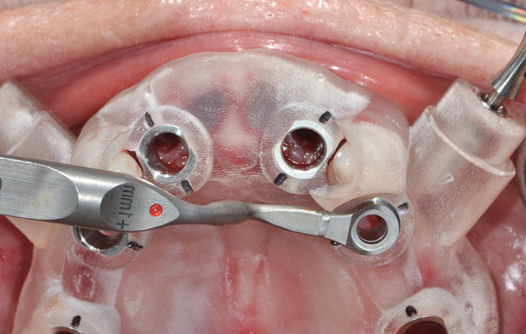

Fig 14. The printed static guide is used to precisely control preparation of osteotomy (Fig 14) and delivery of the implant through the guide (Fig 15).

Figure 14

Fig 15. The printed static guide is used to precisely control preparation of osteotomy (Fig 14) and delivery of the implant through the guide (Fig 15).

Figure 15